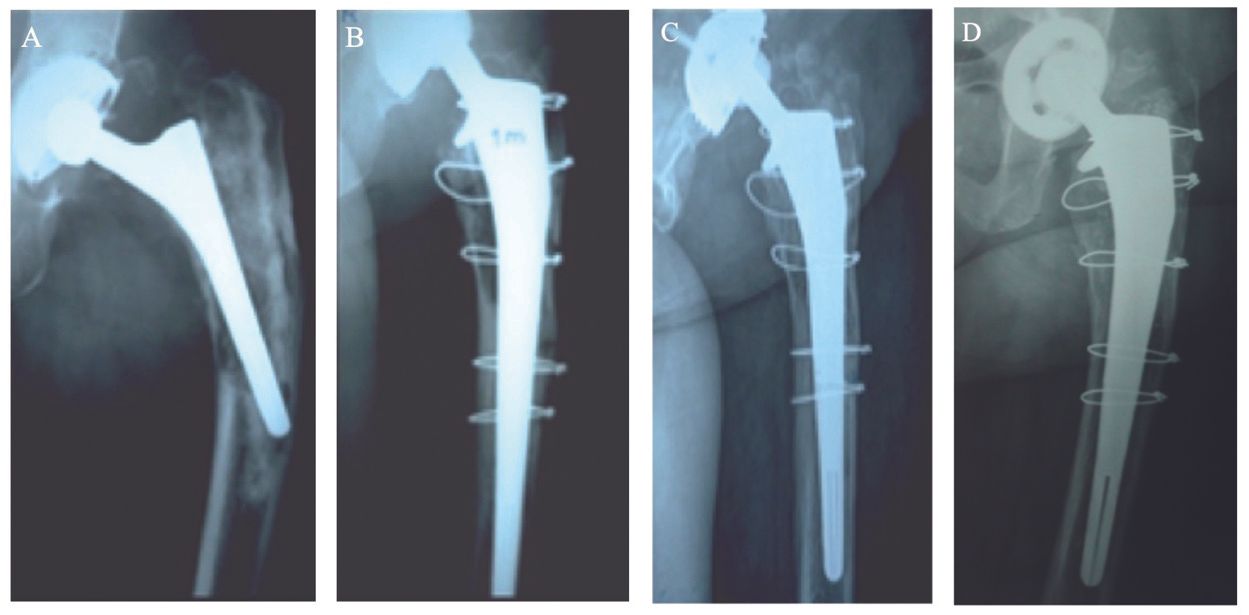

RLs were observed in a total of 38 hips (20%): limited to one Gruen zone in 23 hips (12%), two Gruen zones in 14 hips (8%), and three Gruen zones in only 1 hip (1%). Most RLs were observed in proximal Gruen zones 1 (n=27), 7 (n=13) and 8 (n=4), with very few in middle Gruen zones 2 (n=5) and 6 (n=4) and only one at distal Gruen zone 12. It is worth noting that the distinction between RLs and bone loss sequelae is difficult to ascertain for revision THA stems, particularly if morselised bone graft was required to fill bone defects. Stem migration ≥5mm, compared to the immediate post-revision radiograph, was observed in 7 hips (4%), of which 1 had a Paprosky grade 2, 2 had a grade 3A, 3 had a grade 3B and 1 had a grade 4. The authors observed that, in cases with pre-revision femoral granulomas and osteolysis, post-revision radiographs showed considerable femoral bone reconstruction with nearly complete filling of defects (Figs. 4, 8, 9).

When a femoral revision is performed with HA-coated implants, bone grafting is not essential because the femur has the ability to heal and remodel itself. If grafting is used, autografts are preferred to allografts whenever possible, as long as their use does not cause additional morbidity. It must be noted that such grafts should never be used to stabilize the implant, but only to fill in gaps around a stable stem and, more specifically, to seal the neck section to prevent the ingress of debris. At the calcar level, the main roles of a horseshoe-shaped cortical graft are to protect all HA coating that remains uncovered by the native bone, and to reduce the risk of HA particle migration into the vicinity of the joint space. Moreover, integration of this graft must not be under-evaluated; very often, effective incorporation leads to restoration of normal or near-normal femoral bone stock. The KAR prosthesis is available only with a collar that contributes to stabilization of such a graft (Fig. 4).

For similar reasons, a collared metaphyseal segment can be used with the REEF stem. To achieve osseointegration of bioactive implants, the coating of the stem must be in contact with reactive and living bone to enable effective bonding of the HA layer. Therefore, the CORAIL or the KAR stem must not be implanted using bone compaction techniques that require the use of compacted allograft. In the case of metaphyseal expansion, it is better to perform a longitudinal reduction osteotomy to move the remaining cortices closer onto the implant surface using cerclage wires, rather than to fill in the gap with allografts.